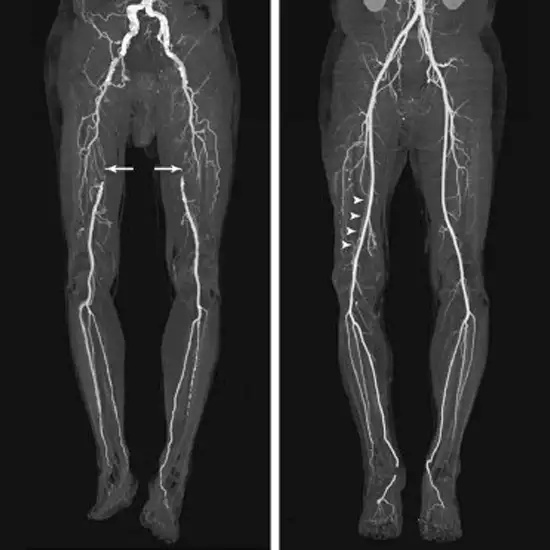

CT Angiography Venous Lower Limb is an imaging scan that is performed to evaluate the Venous (type of blood vessels that return the deoxygenated blood from organs to the heart) in the lower limb. Doctors recommend this scan for a clear diagnosis of the problem with blood vessels in the lower limb. Contrast media is given to the patient to get a detailed picture of vessels.

CT Angiography Venous Lower Limb is a diagnostic imaging technique that is used to visualise the venous structures of the lower limb. The diagnostic scan is used to examine the Venous flow in your lower limbs. The test uses a special contrast media that is given to you through the intravenous route to help visualise the vessels in a clear manner.